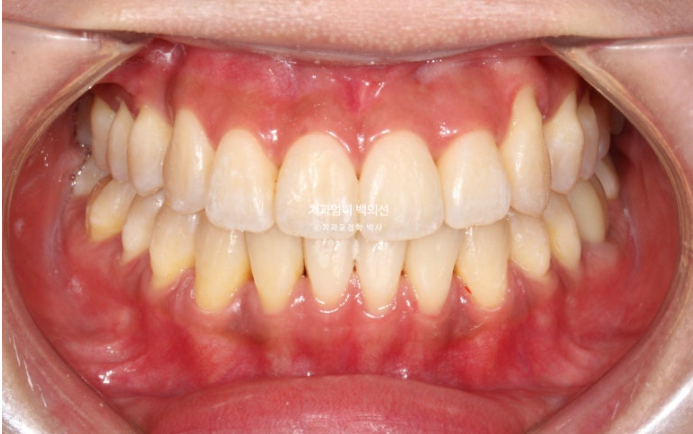

23.09~25.03

초진 3mm의 중심선 불일치가 해결되었습니다.

윗니가 아랫니를 덮는 양이 안정적입니다.

잘 내려와준 덧니입니다.

앞니가 거꾸로 물리던 부분도 정상교합을 찾았습니다